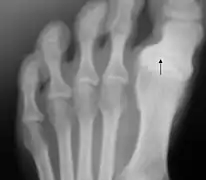

Hallux varus

L'hallux varus est une déformation de l'articulation du gros orteil.

Cette déformation inhabituelle peut être congénitale ou acquise à la suite d'un traumatisme. Prise tôt, une réduction manuelle est possible, par le port de semelles par exemple. Sinon, selon l'avancement, le degré de déformation et le niveau d'arthrose, on pourra déplacer le tendon ou faire une arthrodèse.